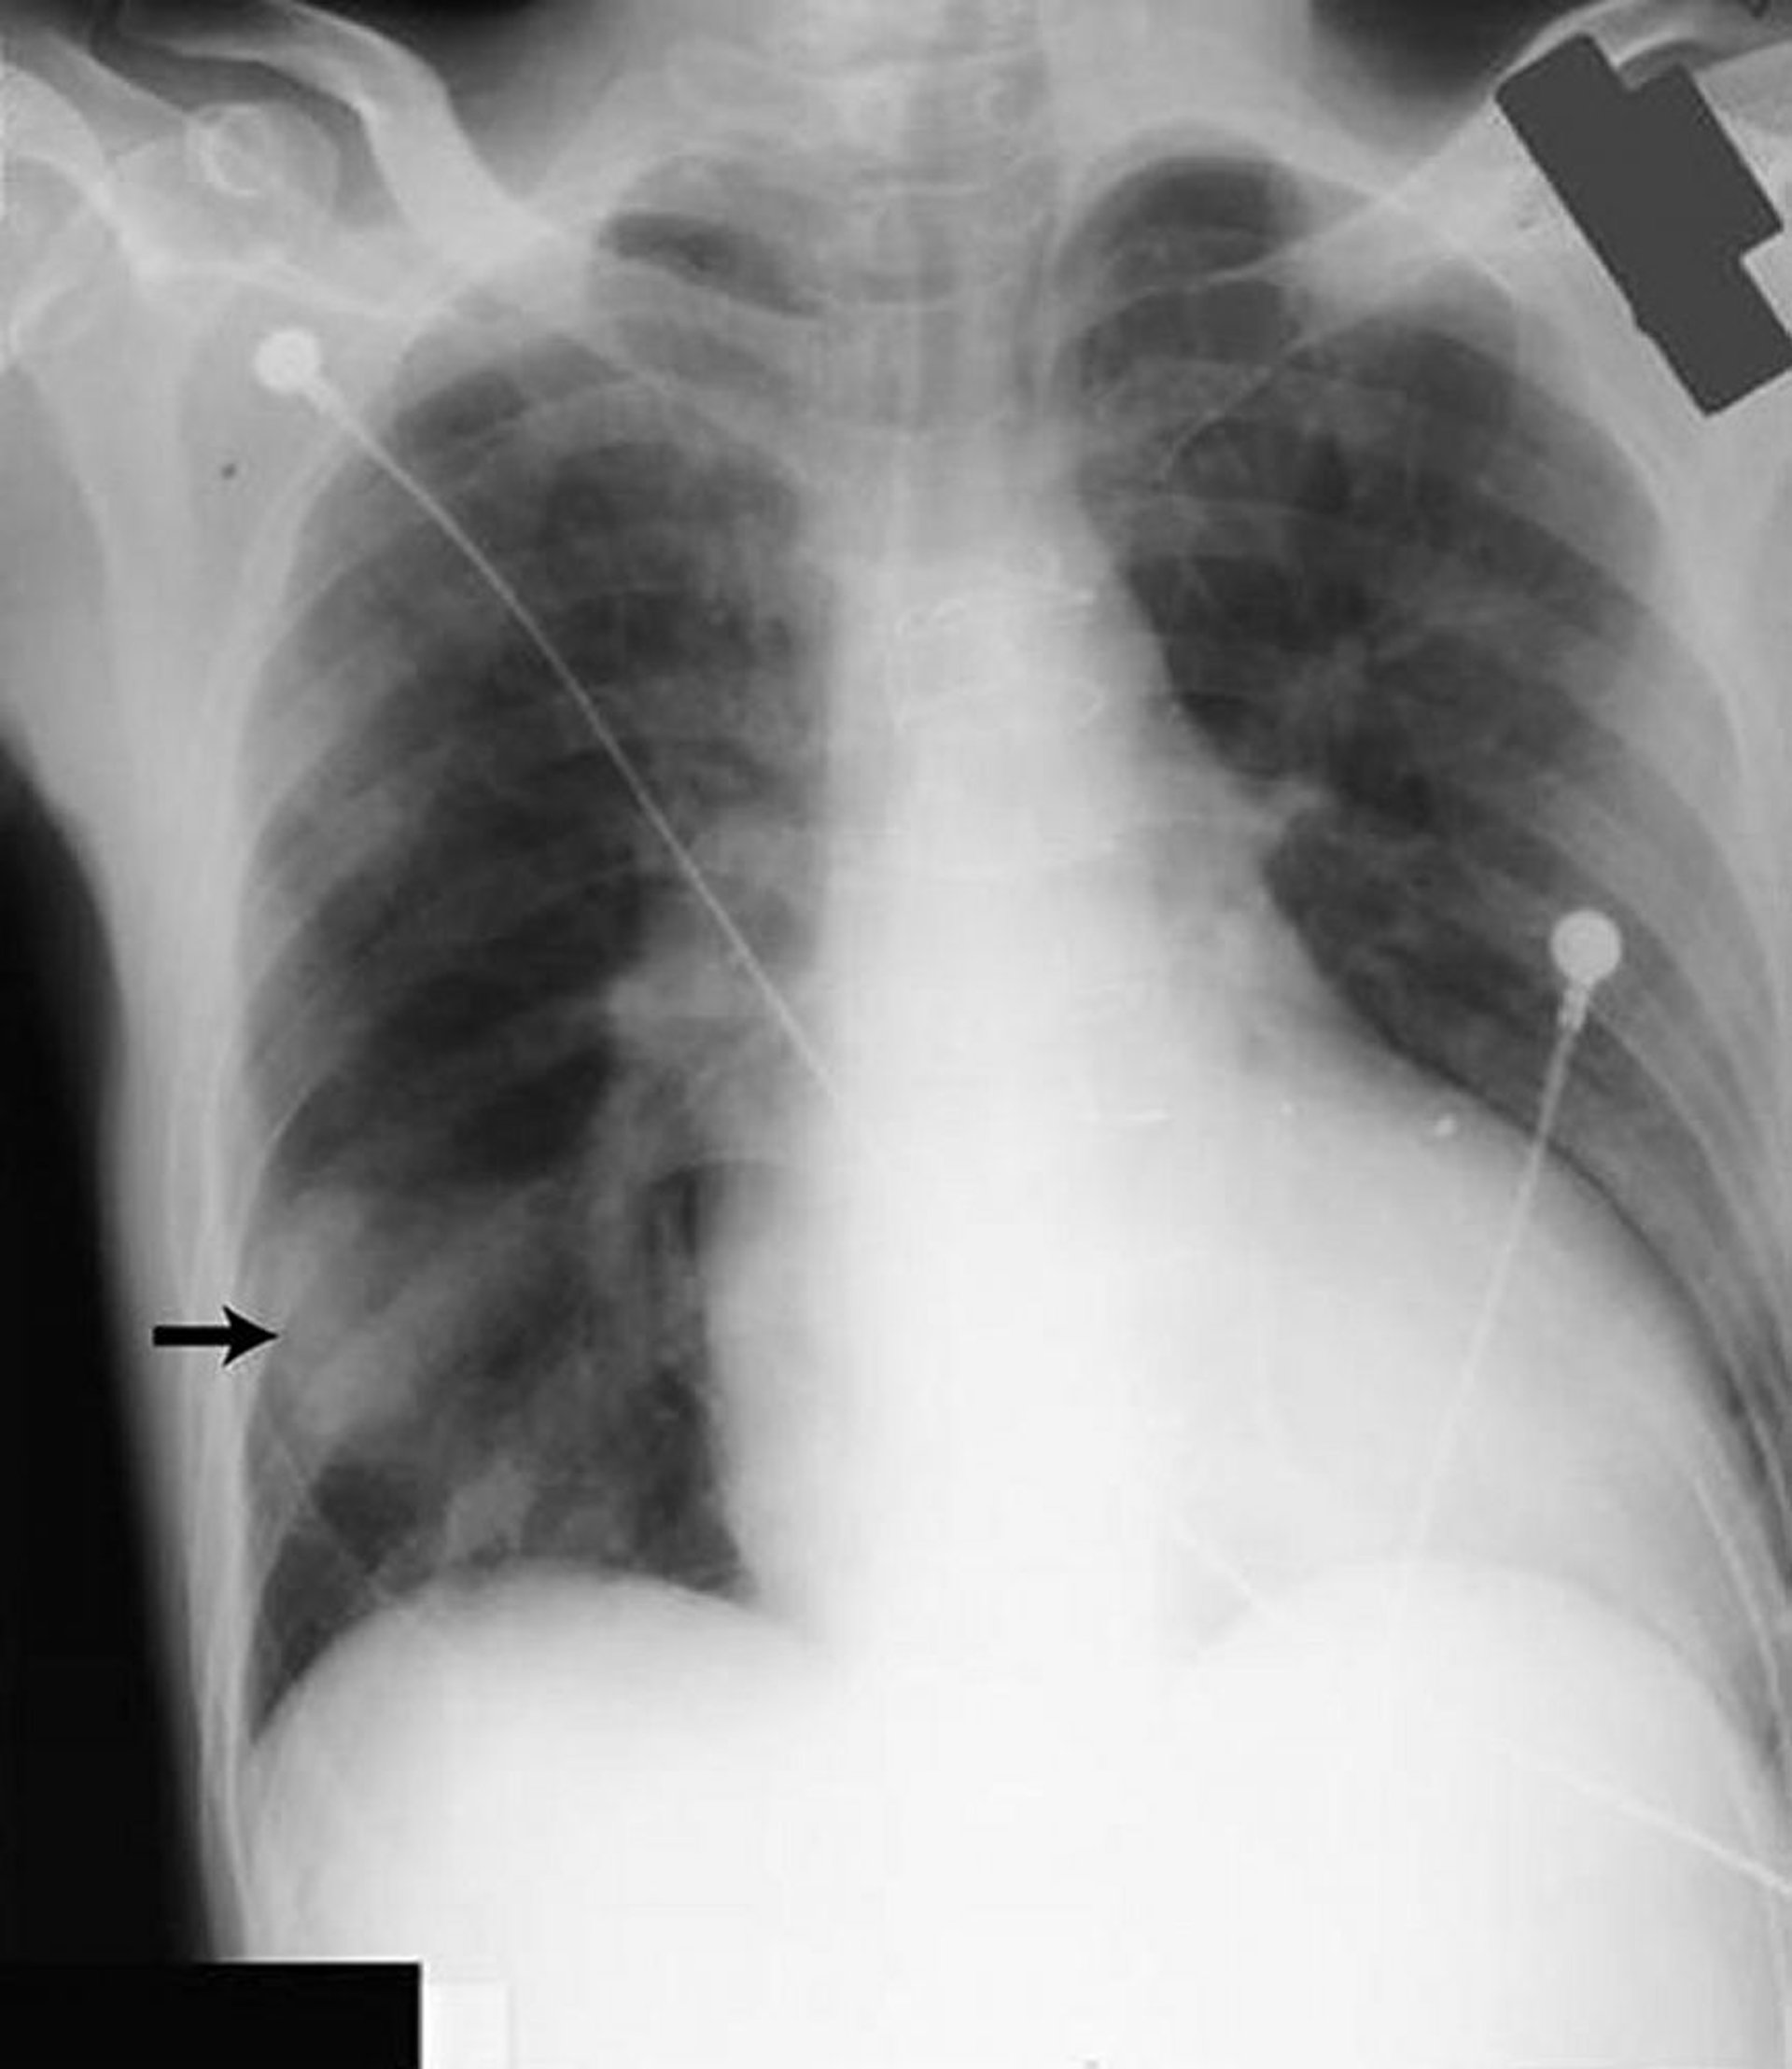

Giả u phổi

Hình mờ ở vùng phổi dưới bên phải (mũi tên) giống như một khối rắn nhưng được gây ra bởi chất lỏng trong rãnh liên thùy lớn ở bệnh nhân bị suy tim.

Được sự cho phép của nhà xuất bản. Theo Huggins J, Sahn S. Trong Bone's Atlas of Pulmonary and Critical Care Medicine. Biên tập bởi J Crapo. Philadelphia, Current Medicine, 2005.